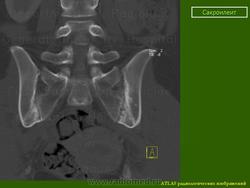

КТ КПС в корональной (а) и аксиальной (b) проекциях: двусторонний сакроилиит I стадии. http://congress-ph.ru/common/htdocs/upload/fm/rar/17/prez/A-10-02.pdf